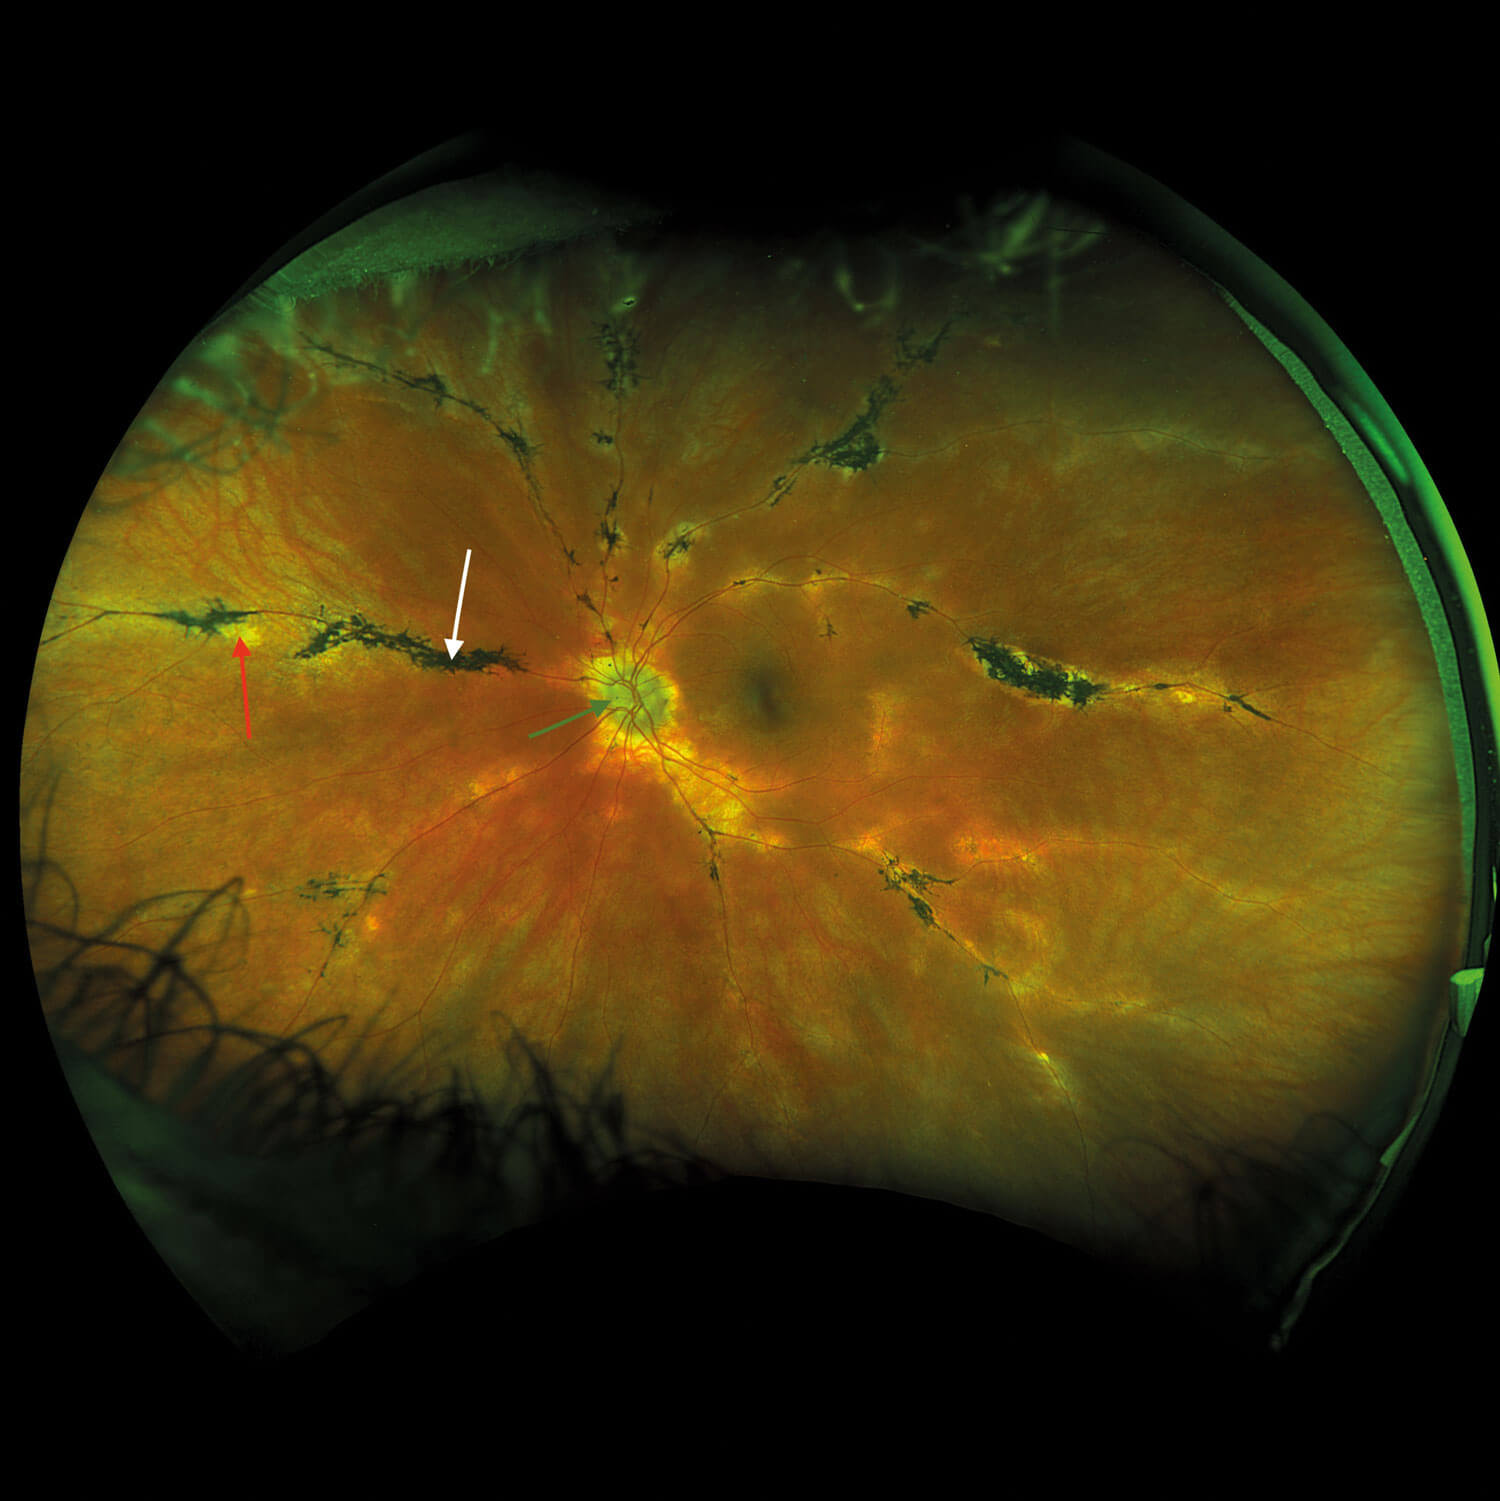

Fundus examination was quite striking in both eyes with bilateral, symmetrical findings. There was evidence of pigment accumulation along the retinal veins, chorioretinal atrophy distributed along the retinal vasculature and elevated, blurred disc margins with a ‘lumpy’ appearance in both eyes.

Figures 1a and 1b: Widefield fundus imaging demonstrating pigment accumulation along the retinal veins (white arrows), chorioretinal atrophy (red arrows) and disc drusen (green arrows).

Widefield fundus imaging demonstrated these clinical findings (Figures 1a, 1b). Fundus autofluorescence showed hypo- autofluorescence in the areas of pigment accumulation and hyperautofluorescence in the areas of chorioretinal atrophy (Figures 2a, 2b). Fundus autofluorescence also showed hyper-autofluorescence at the optic disc indicative of optic nerve drusen. A 30-2 Humphrey visual field test revealed some defects superiorly paracentrally in the right eye. In the left eye there was a more significant field defect with an inferior and superior arcuate defect noted.